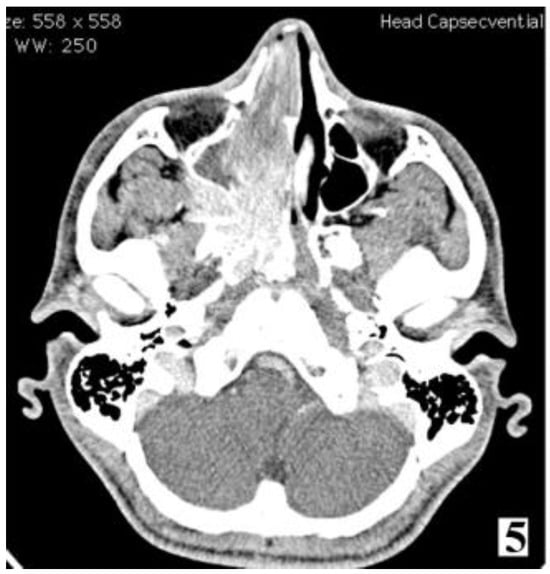

Figure 7.

Preoperative MRI of a stage IIC juvenile angiofibroma. The Holman-Miller sign (the anterior bowing of the posterior maxillary wall) on the CT scan (part 1).

Figure 8.

Preoperative MRI of a stage IIC juvenile angiofibroma. The Holman-Miller sign (the anterior bowing of the posterior maxillary wall) on the CT scan (part 2).

Computer tomograph imaging studies are the ideal investigation when assessing bone involvement, able to identify options for surgical treatment. A pathognomonic sign is the Holman-Miller sign describing the anterior bowing of the posterior maxillary wall in cases with sphenopalatine fossa invasion [6].

Management of stage IIC cases, with extension into the infratemporal fossa or extension posteriorly to the pterygoid plates, can be done by transnasal approach alone or by a combined approach. Preoperative embolization is mandatory for identifying the vascular feeding source and reducing intraoperative bleeding.